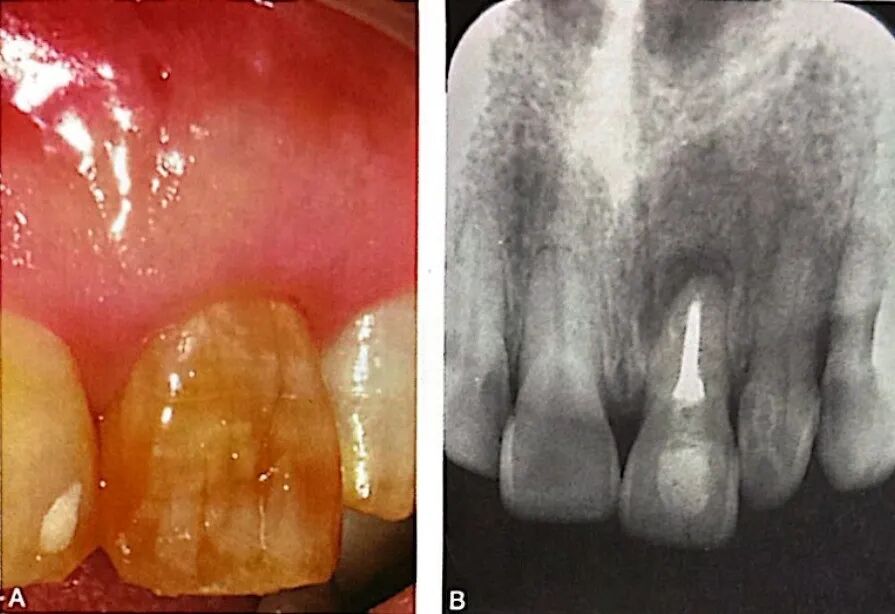

根管侧支通常位于根尖区,少数位于根中段。根尖区以及根中段唇颊侧的根管侧支易诊断,如图5所示,A为口内像颊侧面观示左上中切牙根中段窦道(箭头);B为牙胶示踪根尖片,示窦道来源于牙根中段远中;C为左上颌中切牙行显微根尖外科手术,切开翻瓣牵拉见颊侧根中段骨质缺损;D为刮治后染色见根管侧支;E为根管侧支逆行预备和充填;F为术后根尖片;G为偏角投照根尖片示充填后侧支(箭头);H为术后4个月随访口内像示牙龈和牙槽黏膜正常根尖片,可见根尖周和根周正常;根中段近远中侧或者舌腭侧的根管侧支易漏诊,应使用显微口镜反射观察,必要时行意向再植术,患牙微创完整拔出后在体外全面探查。探查时,根管侧支可有不同着色,蓝黑色(未充填)最为常见,其他有白色(糊剂充填)和黄色、红色、蓝色等(牙胶充填)。